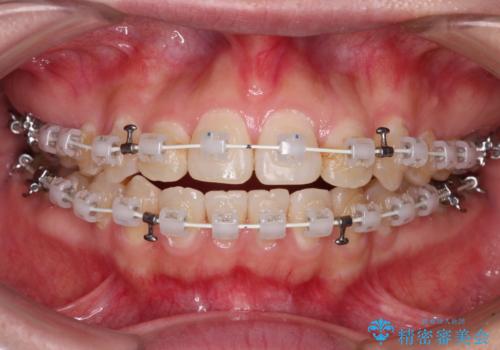

- 審美装置

- 2年1ヶ月

デコボコはあっという間に改善されましたが、開咬の改善に時間がかかりました。

舌の突出癖改善のトレーニングをしっかりと行っていただき、上下前歯が接触する咬み合わせを達成することができました。